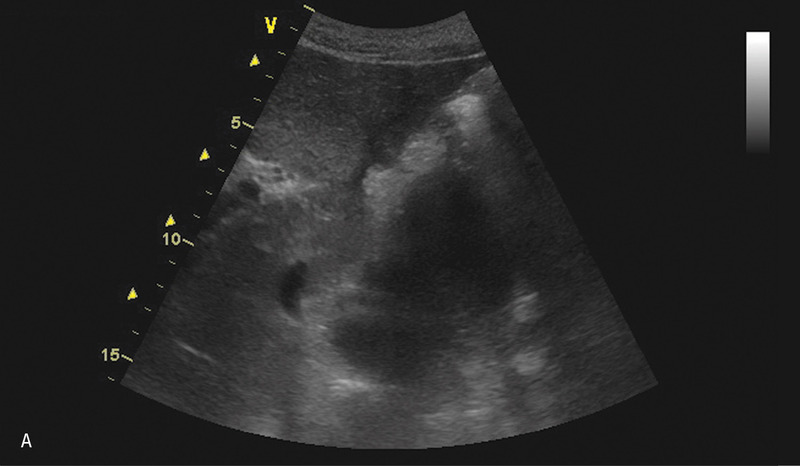

Po kolejnych 3 tygodniach nastąpiło nasilenie dolegliwości sugerujących zaostrzenie zapalenia (wymioty, bóle brzucha, wzdęcie). Pacjenta ponownie przyjęto na oddział chirurgiczny. Rozpoznanie nawrotu zapalenia potwierdzono w badania laboratoryjnych. Wykonano badanie USG, które wykazało obecność kilku zbiorników płynu w śródbrzuszu, w rzucie trzustki oraz po stronie lewej w nadbrzuszu i w lewej jamie opłucnowej (ryc. 2).

Rycina 2. Badanie USG jamy brzusznej. A. Przekrój poprzeczny przez nadbrzusze. Widoczny hipoechogeniczny zbiornik płynu w rzucie głowy trzustki, przesłonięty powierzchownie przez dwunastnicę. B. Przekrój podłużny przez nadbrzusze. Widoczny opisywany grubościenny zbiornik płynu w śródbrzuszu. W centralnej części widoczne zmiany otoczone płynem naczynia. C. Przekrój podłużny przez lewe podżebrze. Widoczne kolejne zbiorniki płynu w otoczeniu śledziony oraz w rzucie trzonu żołądka.